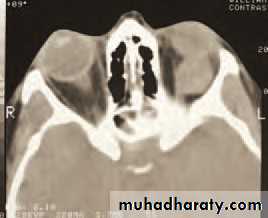

• Infective disorders

• Orbital cellulitis is a serious condition which can cause blindness and may spread to cause a brain abscess. The infection often arises from an adjacent ethmoid sinus. The commonest causative organism is Haemophilus influenzae. The patient presents with:

• a painful eye;

• periorbital inflammation and swelling; mild proptosis

• reduced eye movements;

• conjunctival injection;

• possible visual loss;

• systemic illness and pyrexia.

• An MRI or CT scan is helpful in diagnosis and in planning treatment (Fig. 4.2). The condition usually responds to intravenous broad spectrum antibiotics. It may be necessary to drain an abscess or decompress the orbit particularly if the optic nerve is compromised. Optic nerve function must be closely watched, monitoring acuity, colour vision and testing for a relative afferent pupillary defect. Orbital decompression is usually performed with the help of an ENT specialist.